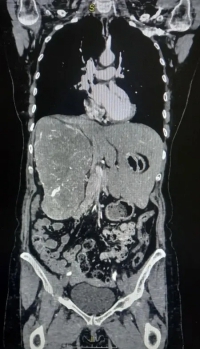

Хирурги Волгоградского областного онкологического диспансера (ГБУЗ ВОКОД) провели уникальную операцию, в ходе которой столкнулись с редкой анатомической картиной: гигантское новообразование почки фактически вытеснило жизненно важные органы с их привычных мест. Опухоль настолько заполнила пространство, что печень пациентки была полностью смещена из правой части брюшной полости в левую.

Как сообщили в областном онкодиспансере, пациентка длительное время жаловалась на тупые боли в поясничной области и тяжесть в животе. По результатам проведенной компьютерной томографии с контрастированием было установлено, что опухоль практически полностью занимала правую половину брюшной полости, смещая печень. На фоне этого, функция самой правой почки была практически утрачена, о чем свидетельствовала динамическая сцинтиграфия. Размеры опухоли составляли: 16,5х11,5х21,1 см.